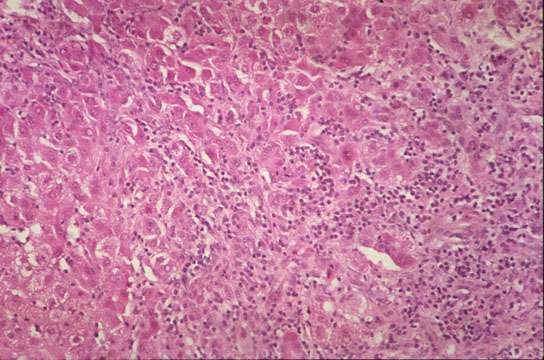

Piecemeal necrosis

Fig 59 - PIECEMEAL NECROSIS: In a patient with chronic active hepatitis B. Notice the disruption of the limiting periportal plate by dense mononuclear cell infiltrate which surrounds hepatocytes (peripolesis).

Portal inflammation may also be accompanied with bile extravasates, granulomas, purulent exudate, destruction of bile ducts, ductular reaction, fibrosis and may extravasate into the periportal liver parenchyma thus disrucpting the periportal limiting plate of hepatocytes. And from there, it may spread to the central acinar area and even reach an adjacent portal field to form a porto-portal septum. In this sequence a peculiar relationsh between inflammatory cells and hepatocytes develops at the parenchymal/mesenchymal interface such as periphery of portal fields and periphery of newly formed inflammatory septa. There is destruction of single or small groups of hepatocytes which are surrounded by and in close membrane contact with lymphocytes and macrophages. The phenomenon has been called:

"PIECEMEAL NECROSIS"

The surrounding and membrane contact between lymphocytes and hepatocyte which goes under the name of "PERIPOLESIS" is the hallmark of piecemeal necrosis. When lymphocytes penetrate a hepatocyte or any other cell, the phenomenon is called "EMPERIPOLESIS". In piecemeal necrosis the hepatocytes may become necrotic or apoptotic. Others may become hyperplastic and grow in "ROSETTES" surrounded by a rim of fibrous tissue. Ductular proliferation may occur. The portal field undergoes fibrous expansion.